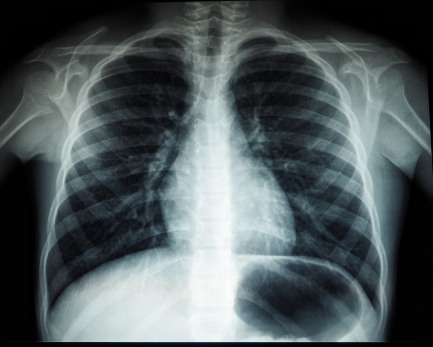

Онколог назвал семь самых первых симптомов рака легких

Главный внештатный специалист по онкологии министерства здравоохранения Самарской области, кандидат медицинских наук Александр Фролов назвал первые признаки рака легких. По словам врача, на ранних стадиях болезнь имеет скрытое течение, а начальные симптомы проявляются мере прогрессирования опухоли.

Это поверхностное дыхание, боль в груди, выделение мокроты с кровью, охриплость голоса, рецидивирующие легочные инфекции (пневмония, бронхиты), постоянное чувство усталости и беспричинная потеря веса.

Фролов рассказал, что сегодня для выявления новообразований все шире используется компьютерная томография, а для уточняющей диагностики - бронхоскопия.

- Если вы заметили тревожные признаки, которые не проходят более трех недель - кашель, одышку или обильную мокроту - немедленно обратитесь к врачу и пройдите соответствующие обследования, - сказал он.